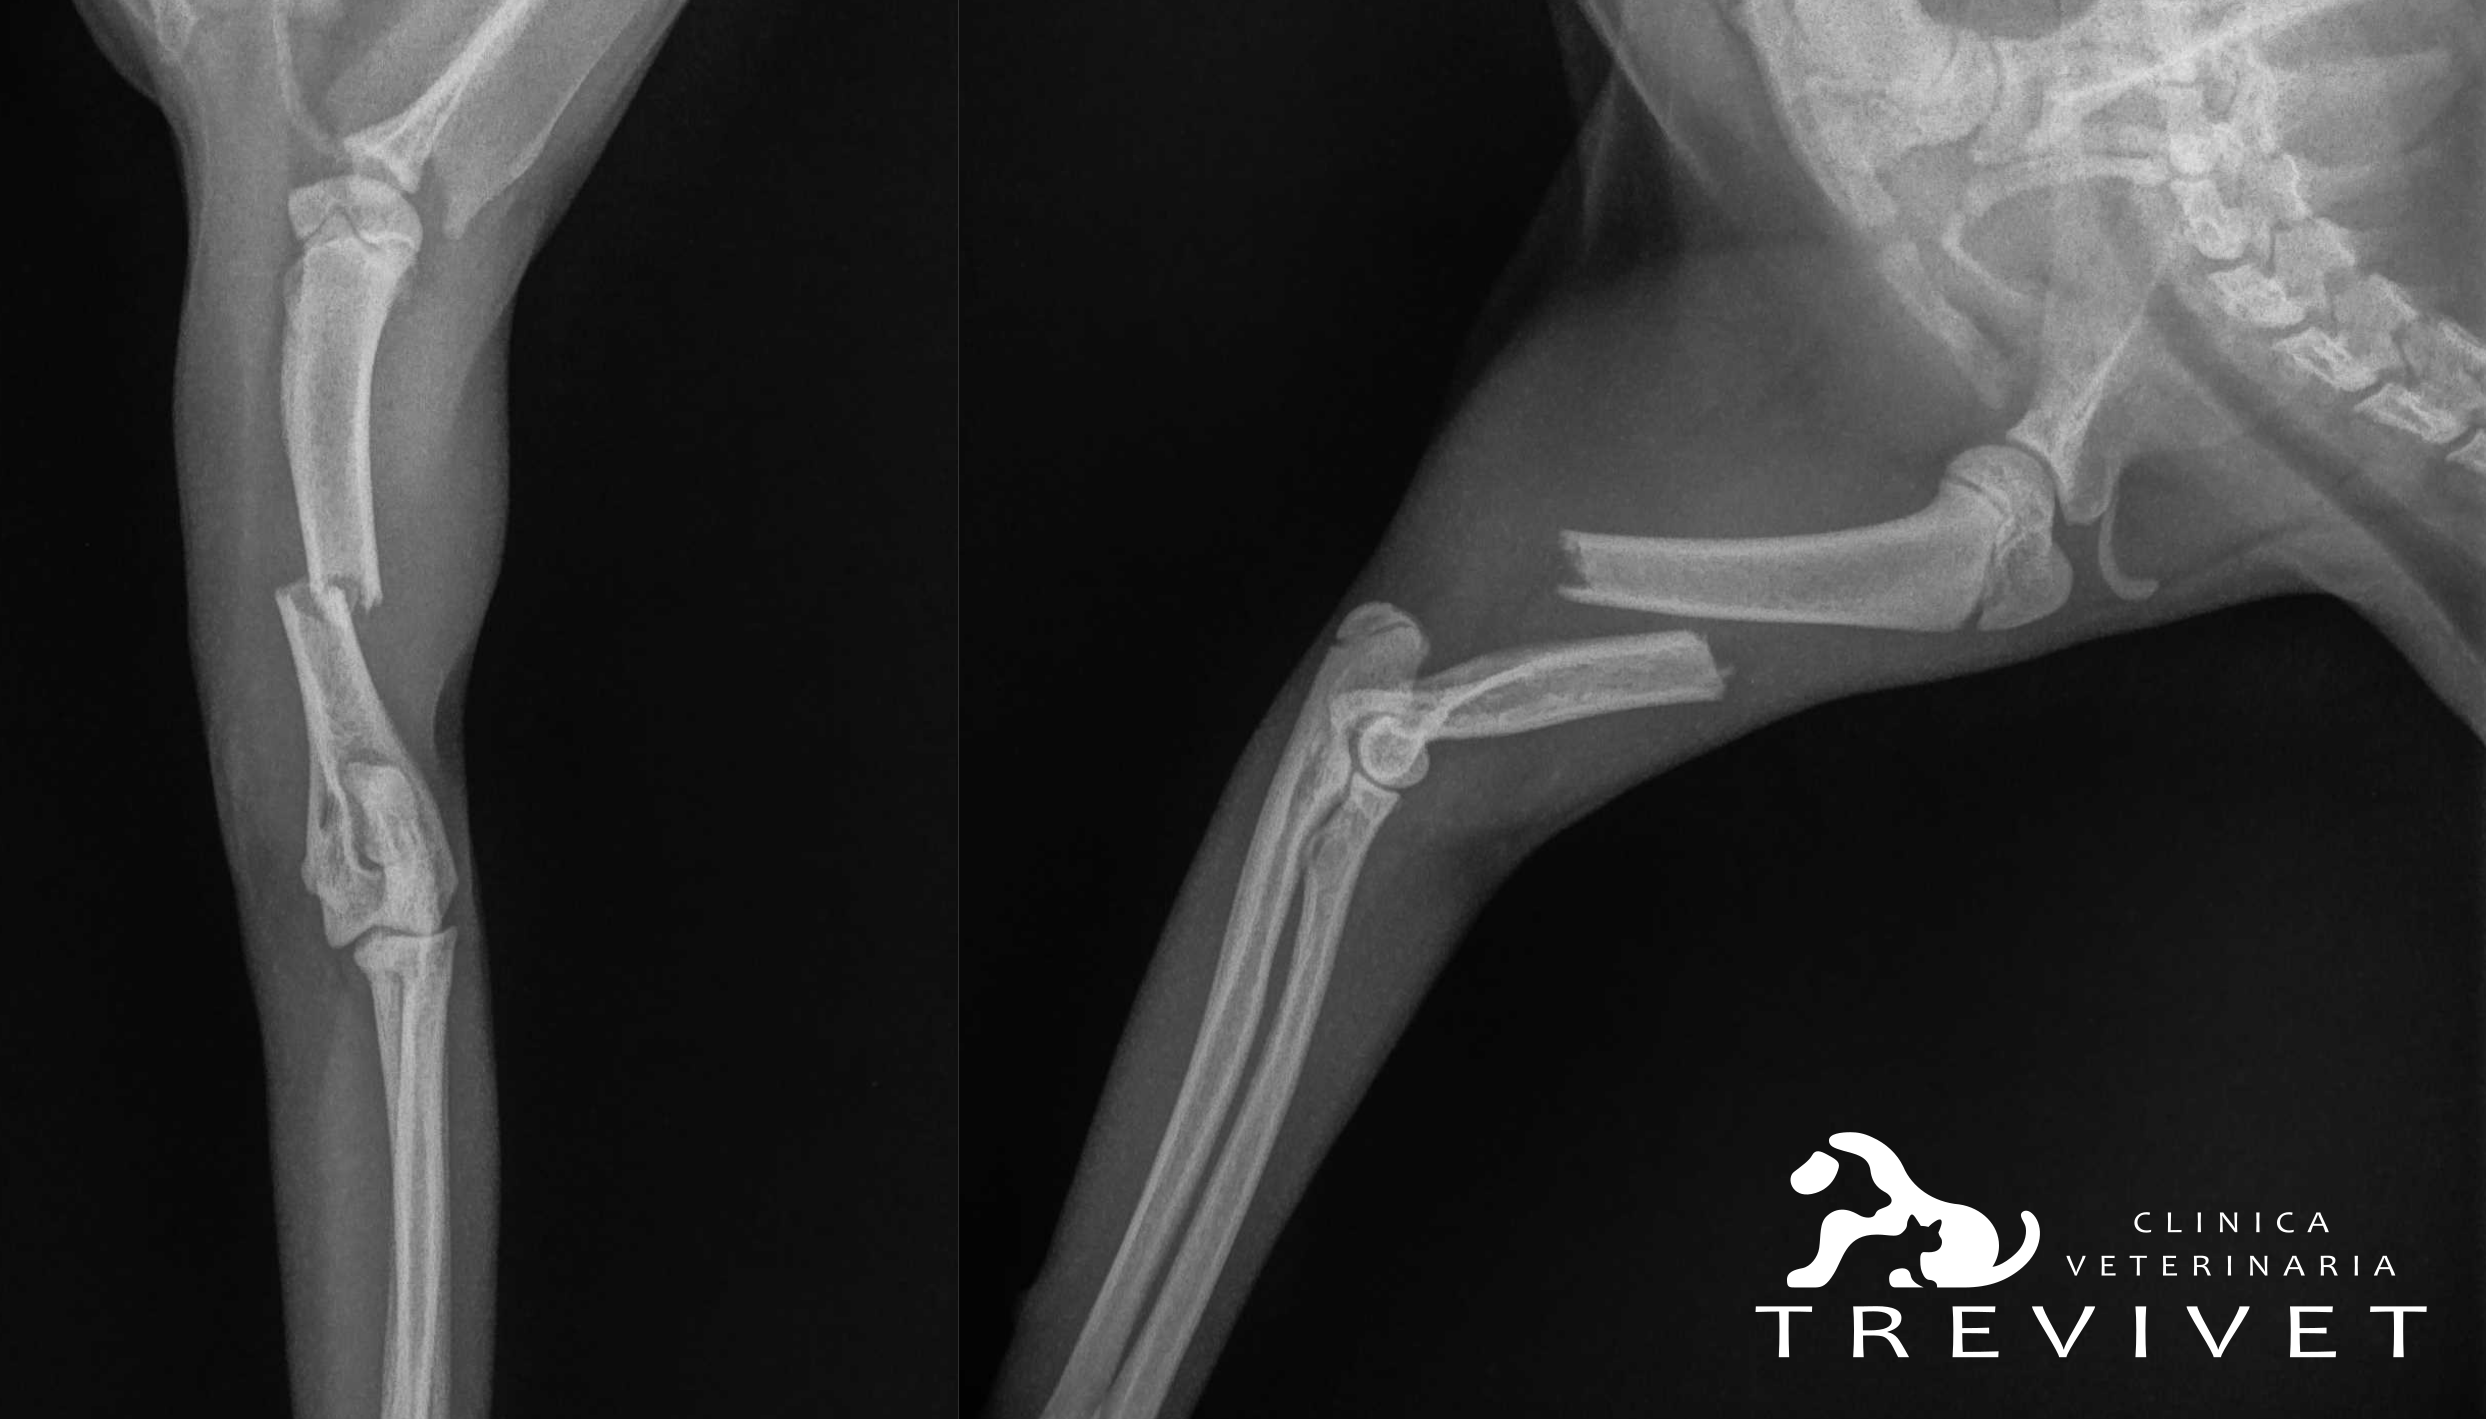

Favy gattina comune europea di circa 6 mesi, viene portata in visita per una zoppia di 4° grado sull’arto anteriore destro. Alla visita si nota un accorciamento dell’arto più marcato nella zona prossimale con supinazione della mano e mantenimento del dolore profondo. All’esame radiografico in sedazione si evince la presenza di una frattura trasversa dell’omero del 2° terzo medio con contrazione e dislocazione mediale del moncone distale.